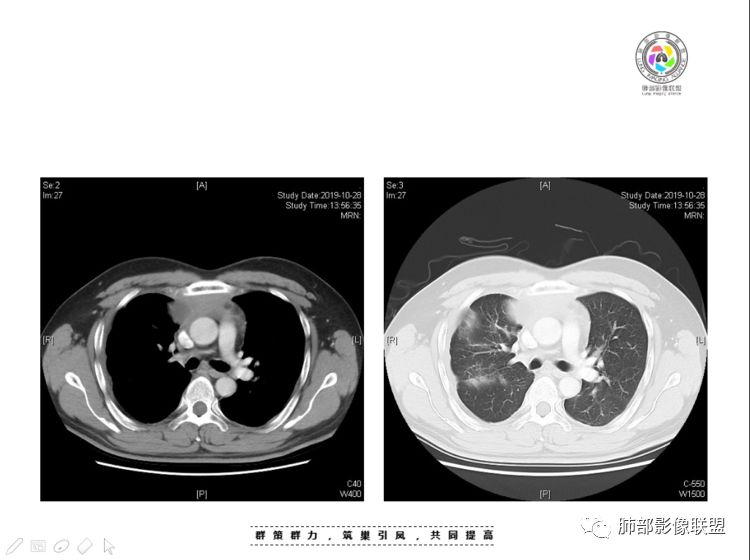

肺内结节,近端支气管堵塞狭窄

整体边缘收缩,部分膨隆

炎性要考虑,但恶性不能排除

1、右肺内病灶,病灶呈结节样,边缘欠规则,局部膨隆,叶间裂胸膜牵拉凹陷,再看相应支气管腔堵塞截断,临床资料胸水中查到癌细胞,均提示病灶倾向恶性,腺癌的病理意见与之相吻合。

2、前纵隔内病灶囊实性混杂密度病灶,囊性病灶主要位于右侧,张力较高,有分隔影,囊壁右侧缘光整,病灶左侧实性部分边界不清明显强化,病灶肺瘤交界面大部分边界清楚,部分模糊。